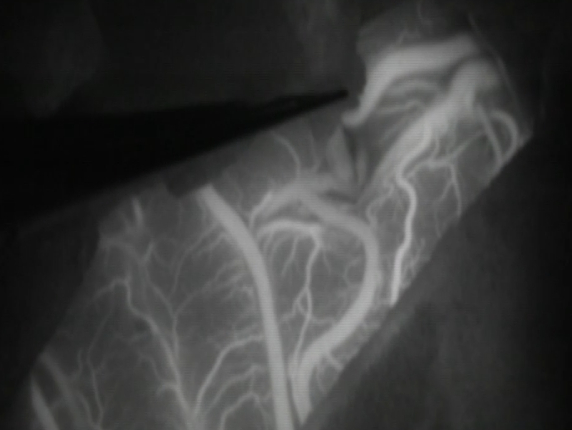

荧光造影显示血流通畅。挑起来看深入脑沟内的另一端(紧挨着的是根静脉):